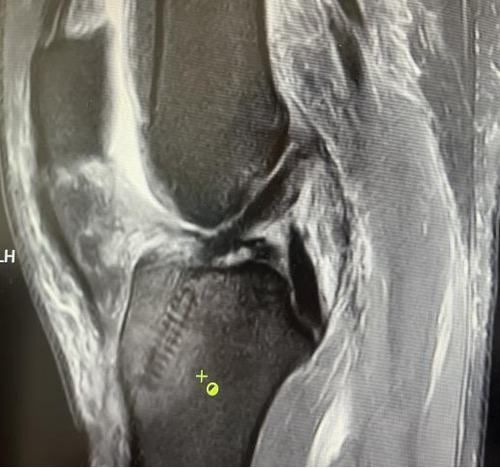

膝關(guān)節(jié)韌帶損傷磁共振

我院骨科三病區(qū)近期收治了4名膝關(guān)節(jié)交叉韌帶損傷患者。25歲的齊先生,因打籃球時不慎扭傷左膝,致右膝腫痛,遂來我院治療;30歲趙先生酷愛足球,扭傷右膝關(guān)節(jié)來我院就診;50歲的張先生、42歲劉先生因騎車滑倒摔傷、膝關(guān)節(jié)腫痛不適、活動受限,收治入院。骨科三病區(qū)李鵬主任團隊詳細查體以及完善影像學檢查后進行診斷:幾位患者共同診斷均有“前交叉韌帶損傷”,不同程度合并有“半月板損傷”、“股骨軟骨損傷”、“內(nèi)側(cè)副韌帶斷裂”。

經(jīng)患者同意后,李鵬主任手術(shù)團隊制定詳細手術(shù)方案。手術(shù)如期進行,經(jīng)團隊密切配合,對幾位患者分別順利完成關(guān)節(jié)鏡下膝關(guān)節(jié)鏡鏡檢、關(guān)節(jié)清理、股薄肌半腱肌取腱移植術(shù)、前交叉韌帶重建術(shù)、軟骨損傷微骨折術(shù)、半月板縫合修整術(shù)等。